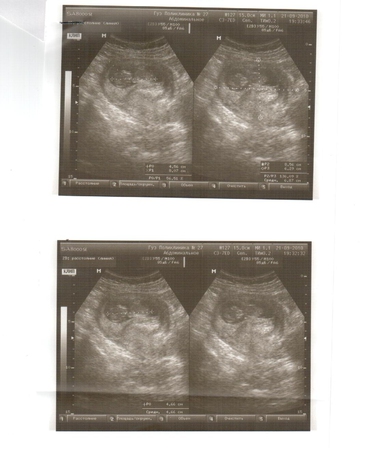

наша первая фотография

Беременностьвчера наконец то сходили на УЗИ! в общем все хорошо, тонус есть, но совсем немного. ребетенок просто прелесть. сначала спокойно лежал, дал посмотреть сердечко, сфотографировать, а потом начал активно вертеться! отвернулся спинкой, показал ножки, такие маленькие, хорошенькие ступни)))) так мило. Муж стоял как завороженный смотрел на монитор! потом долго все переваривал, и только уже уходя на работу выдал, что очень рад, что ему интересно и необычно было.... ну и то, что переживает, из-за того, что врач ему сказала, что есть угроза....ну а она ему это сказала, чтобы заботился больше, т.к. знакомая наша)))